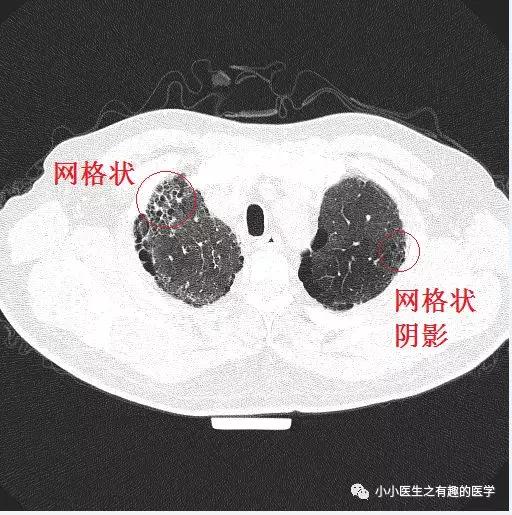

经典的间质性肺炎,就是一张网!

1.胸膜下2.网格状很多间质性肺炎,都有这个特征,是间质性肺炎的入门知识,也是很重要的知识。

假如一个患者结缔组织病,双肺多发病变,但是,胸膜下没有病灶,首先不考虑间质性肺炎,要考虑其他疾病。